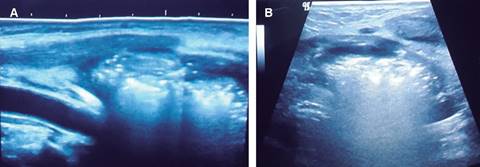

Masculino de 60 años de edad con diabetes mellitus de cinco años de evolución no controlada, sin otros antecedentes, relata presentar fiebre y faringitis de 15 días, acompañada de dolor en cuello, faringe, oído izquierdo y región retroauricular izquierda; manejado por facultativo con AINE y antibiótico no especificado, llegando el dolor a ser intolerable por lo que acude a la institución; a la exploración física: signos vitales normales, fiebre de 38.5 oC; eritema en cara anterolateral izquierda de cuello, dolor intenso en 10/10 en escala visual análoga (EVA 1-10) a la palpación de lóbulo izquierdo de tiroides, con irradiación a cara anterior de tórax, región supraclavicular y oído izquierdos; resto de exploración normal. Se ingresa, los exámenes de laboratorio mostraron: leucocitosis de 27,000/mm3 con 89% de polimorfonucleares, perfil tiroideo normal y glucosa de 320 mg/dL. Se inició antibióticos empíricos con linezolid 600 mg IV BID, meropenem 1 g IV TID, clindamicina 300 mg IV QID y control de glucosa con esquema de insulina. Se efectuó ultrasonido de cuello (Figura 1) encontrando: lesiones hiperecoicas con tendencia a la confluencia, extendidas en y alrededor del lóbulo tiroideo izquierdo. La tomografía computarizada mostró: presencia de burbujas en la glándula tiroides y a través de los tejidos blandos cervicales hacia el mediastino superior (Figuras 2 y 3). El tránsito esofágico con trago de bario no reportó presencia de fístula. A los dos días de su ingreso se encontró aumento de volumen del lóbulo izquierdo de tiroides; se efectuó punción guiada por ultrasonido, extrayendo escaso líquido seropurulento para cultivo con resultado de Staphylococcus aureus, a los seis días de hospitalización los leucocitos descendieron a 11,000/mm3. Después de 14 días de tratamiento, con mejoría clínica del dolor, de la glucemia y disminución de leucocitosis, manteniéndose el perfil tiroideo dentro de límites normales, se solicitó nueva tomografía (Figura 4) que mostró persistencia de absceso, por lo que se programó cirugía, drenando material purulento, postoperatorio sin problema; a un mes de postoperatorio, paciente asintomático, con ultrasonido de control normal al igual que perfil tiroideo.

Figura 1: Imágenes de ultrasonido en corte sagital (A) y axial (B) mostrando múltiples lesiones hiperecoicas tendientes a la confluencia, que se extienden en y alrededor del lóbulo tiroideo izquierdo, correspondiendo a tiroiditis supurativa con formación inicial de absceso tiroideo.